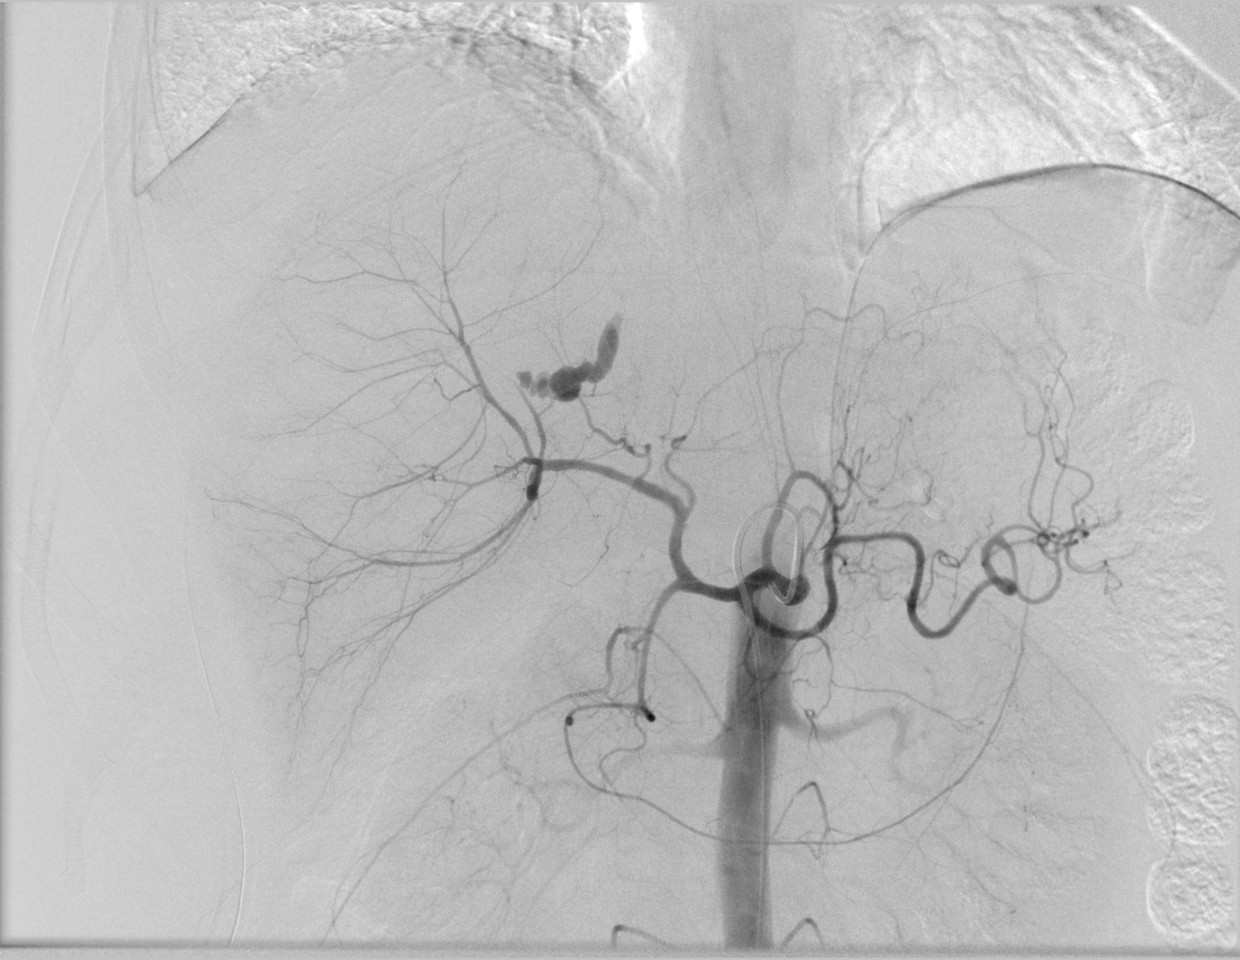

急診外傷肝破裂的介入治療

治療前

治療后